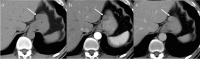

Gastrointestinal stromal tumors (GISTs) originating from the interstitial cells of Cajal in the muscularis propria are the most common mesenchymal tumor of the gastrointestinal tract. Multiple modalities, including computed tomography (CT), magnetic resonance imaging (MRI), fluorodeoxyglucose positron emission tomography, ultrasonography, digital subtraction angiography, and endoscopy, have been performed to evaluate GISTs. CT is most frequently used for diagnosis, staging, surveillance, and response monitoring during molecularly targeted therapy in clinical practice. The diagnosis of GISTs is sometimes challenging because of the diverse imaging findings, such as anatomical location (esophagus, stomach, duodenum, small bowel, colorectum, appendix, and peritoneum), growth pattern, and enhancement pattern as well as the presence of necrosis, calcification, ulceration, early venous return, and metastasis. Imaging findings of GISTs treated with antineoplastic agents are quite different from those of other neoplasms (e.g. adenocarcinomas) because only subtle changes in size are seen even in responsive lesions. Furthermore, the recurrence pattern of GISTs is different from that of other neoplasms. This review discusses the advantages and disadvantages of each imaging modality, describes imaging findings obtained before and after treatment, presents a few cases of complicated GISTs, and discusses recent investigations performed using CT and MRI to predict histological risk grade, gene mutations, and patient outcomes.